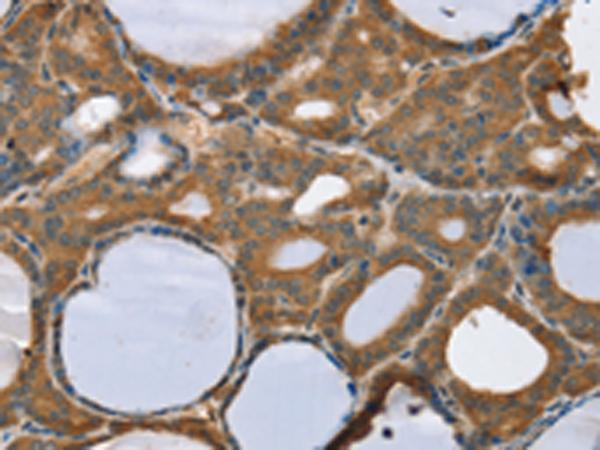

分类: 科研抗体货号: P05257别名: SCP2; SCP-2应用: IHC反应种属: Human, Mouse, Rat